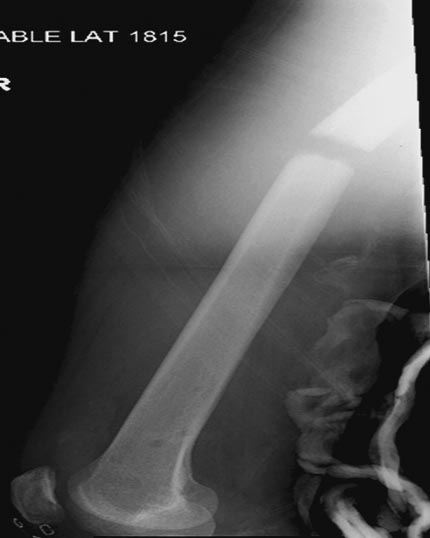

Вложение не в текстовом формате было извлечено…

Имя     : Picture3.jpg

Тип     : image/jpeg

Размер  : 32742 байтов

Описание: отсутствует

Url     : http://weborto.net:8080/pipermail/ortho/attachments/20180407/cb9d5034/attachment-0012.jpg